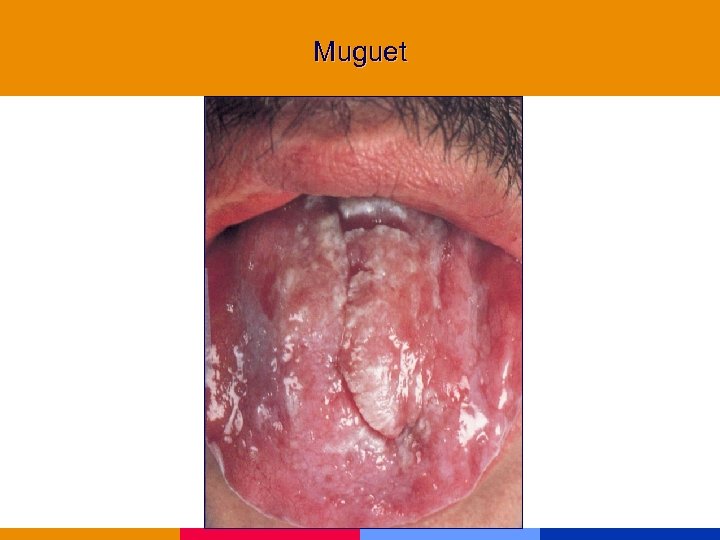

Muguet

Muguet

Muguet

Muguet